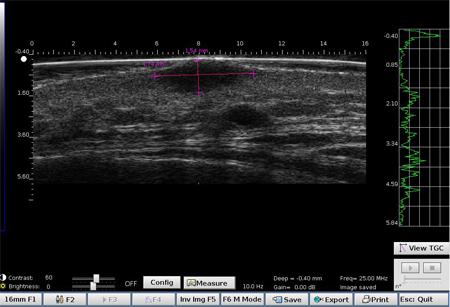

DERMCUP permite la adquisición no invasiva de secciones verticales de la piel in vivo

La dermis es ecogénica. Los ecos provienen de la red de fibras de colágeno y fibras elásticas. En relación a la dermis, las lesiones (tumores, quistes, angiomas …) aparecen como áreas hipoecoicas.

Sonda 2D Muy ergonómica  Fácilmente manipulada  Adquisición de 10 imágenes / s

Adquisición de sonda 3D de 300 imágenes 2D.

Software de post-procesamiento de imágenes

Atys, en colaboración con Creatis (laboratorio de investigación en imagen médica: www.creatis.insa-lyon.fr ) a través de Labcom AtysCrea, ha desarrollado un software de post-procesamiento poderosa imagen grabada por el DERMCUP para la segmentación estructuras (tumores, …) presentes en la dermis.